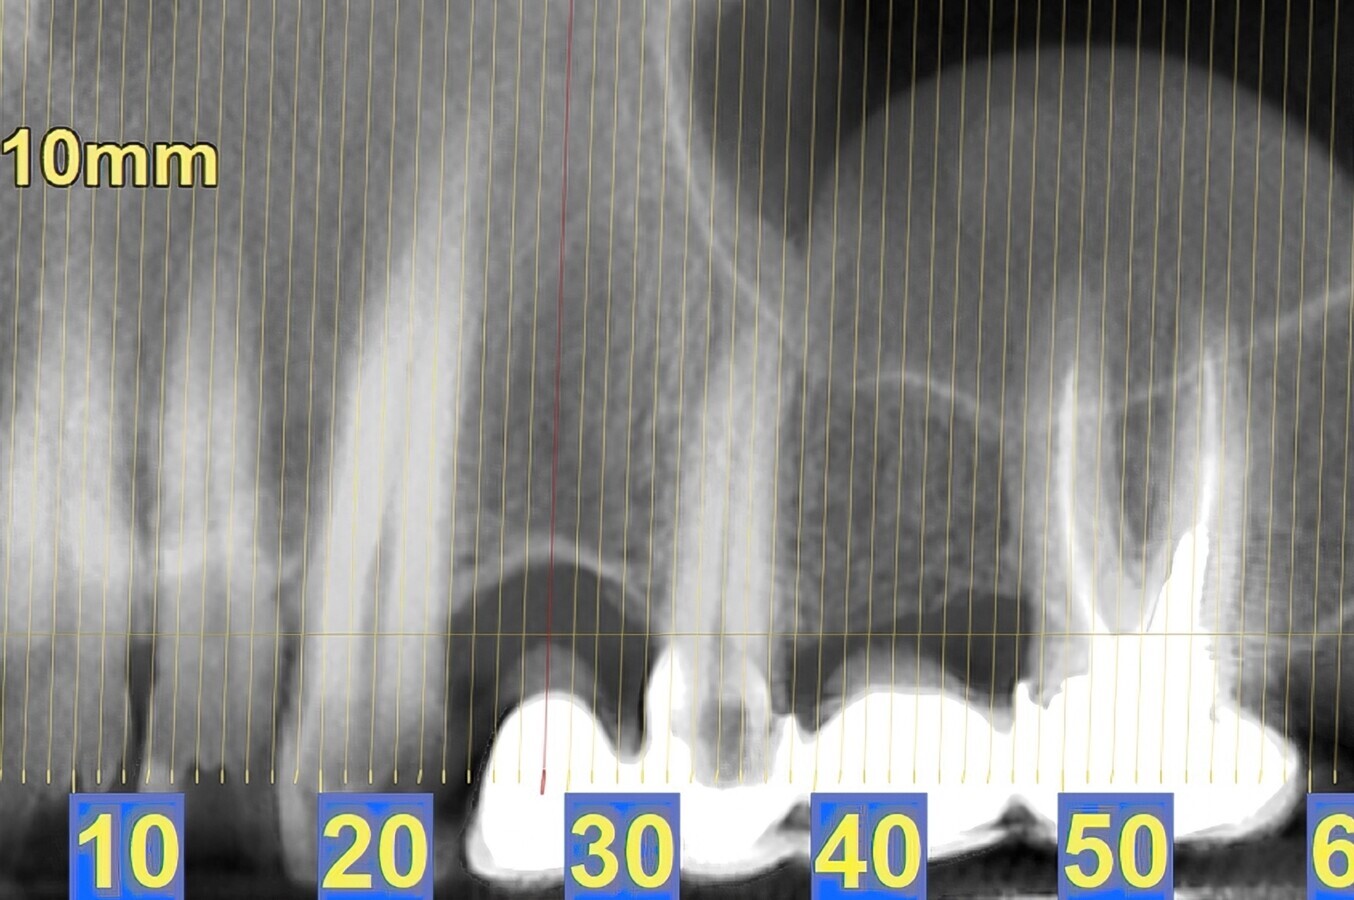

Fig. 3. Situación radiográfica después de la colocación del implante.

Fig. 4. Situación radiográfica después de la colocación de la corona final, seguimiento de tres meses.